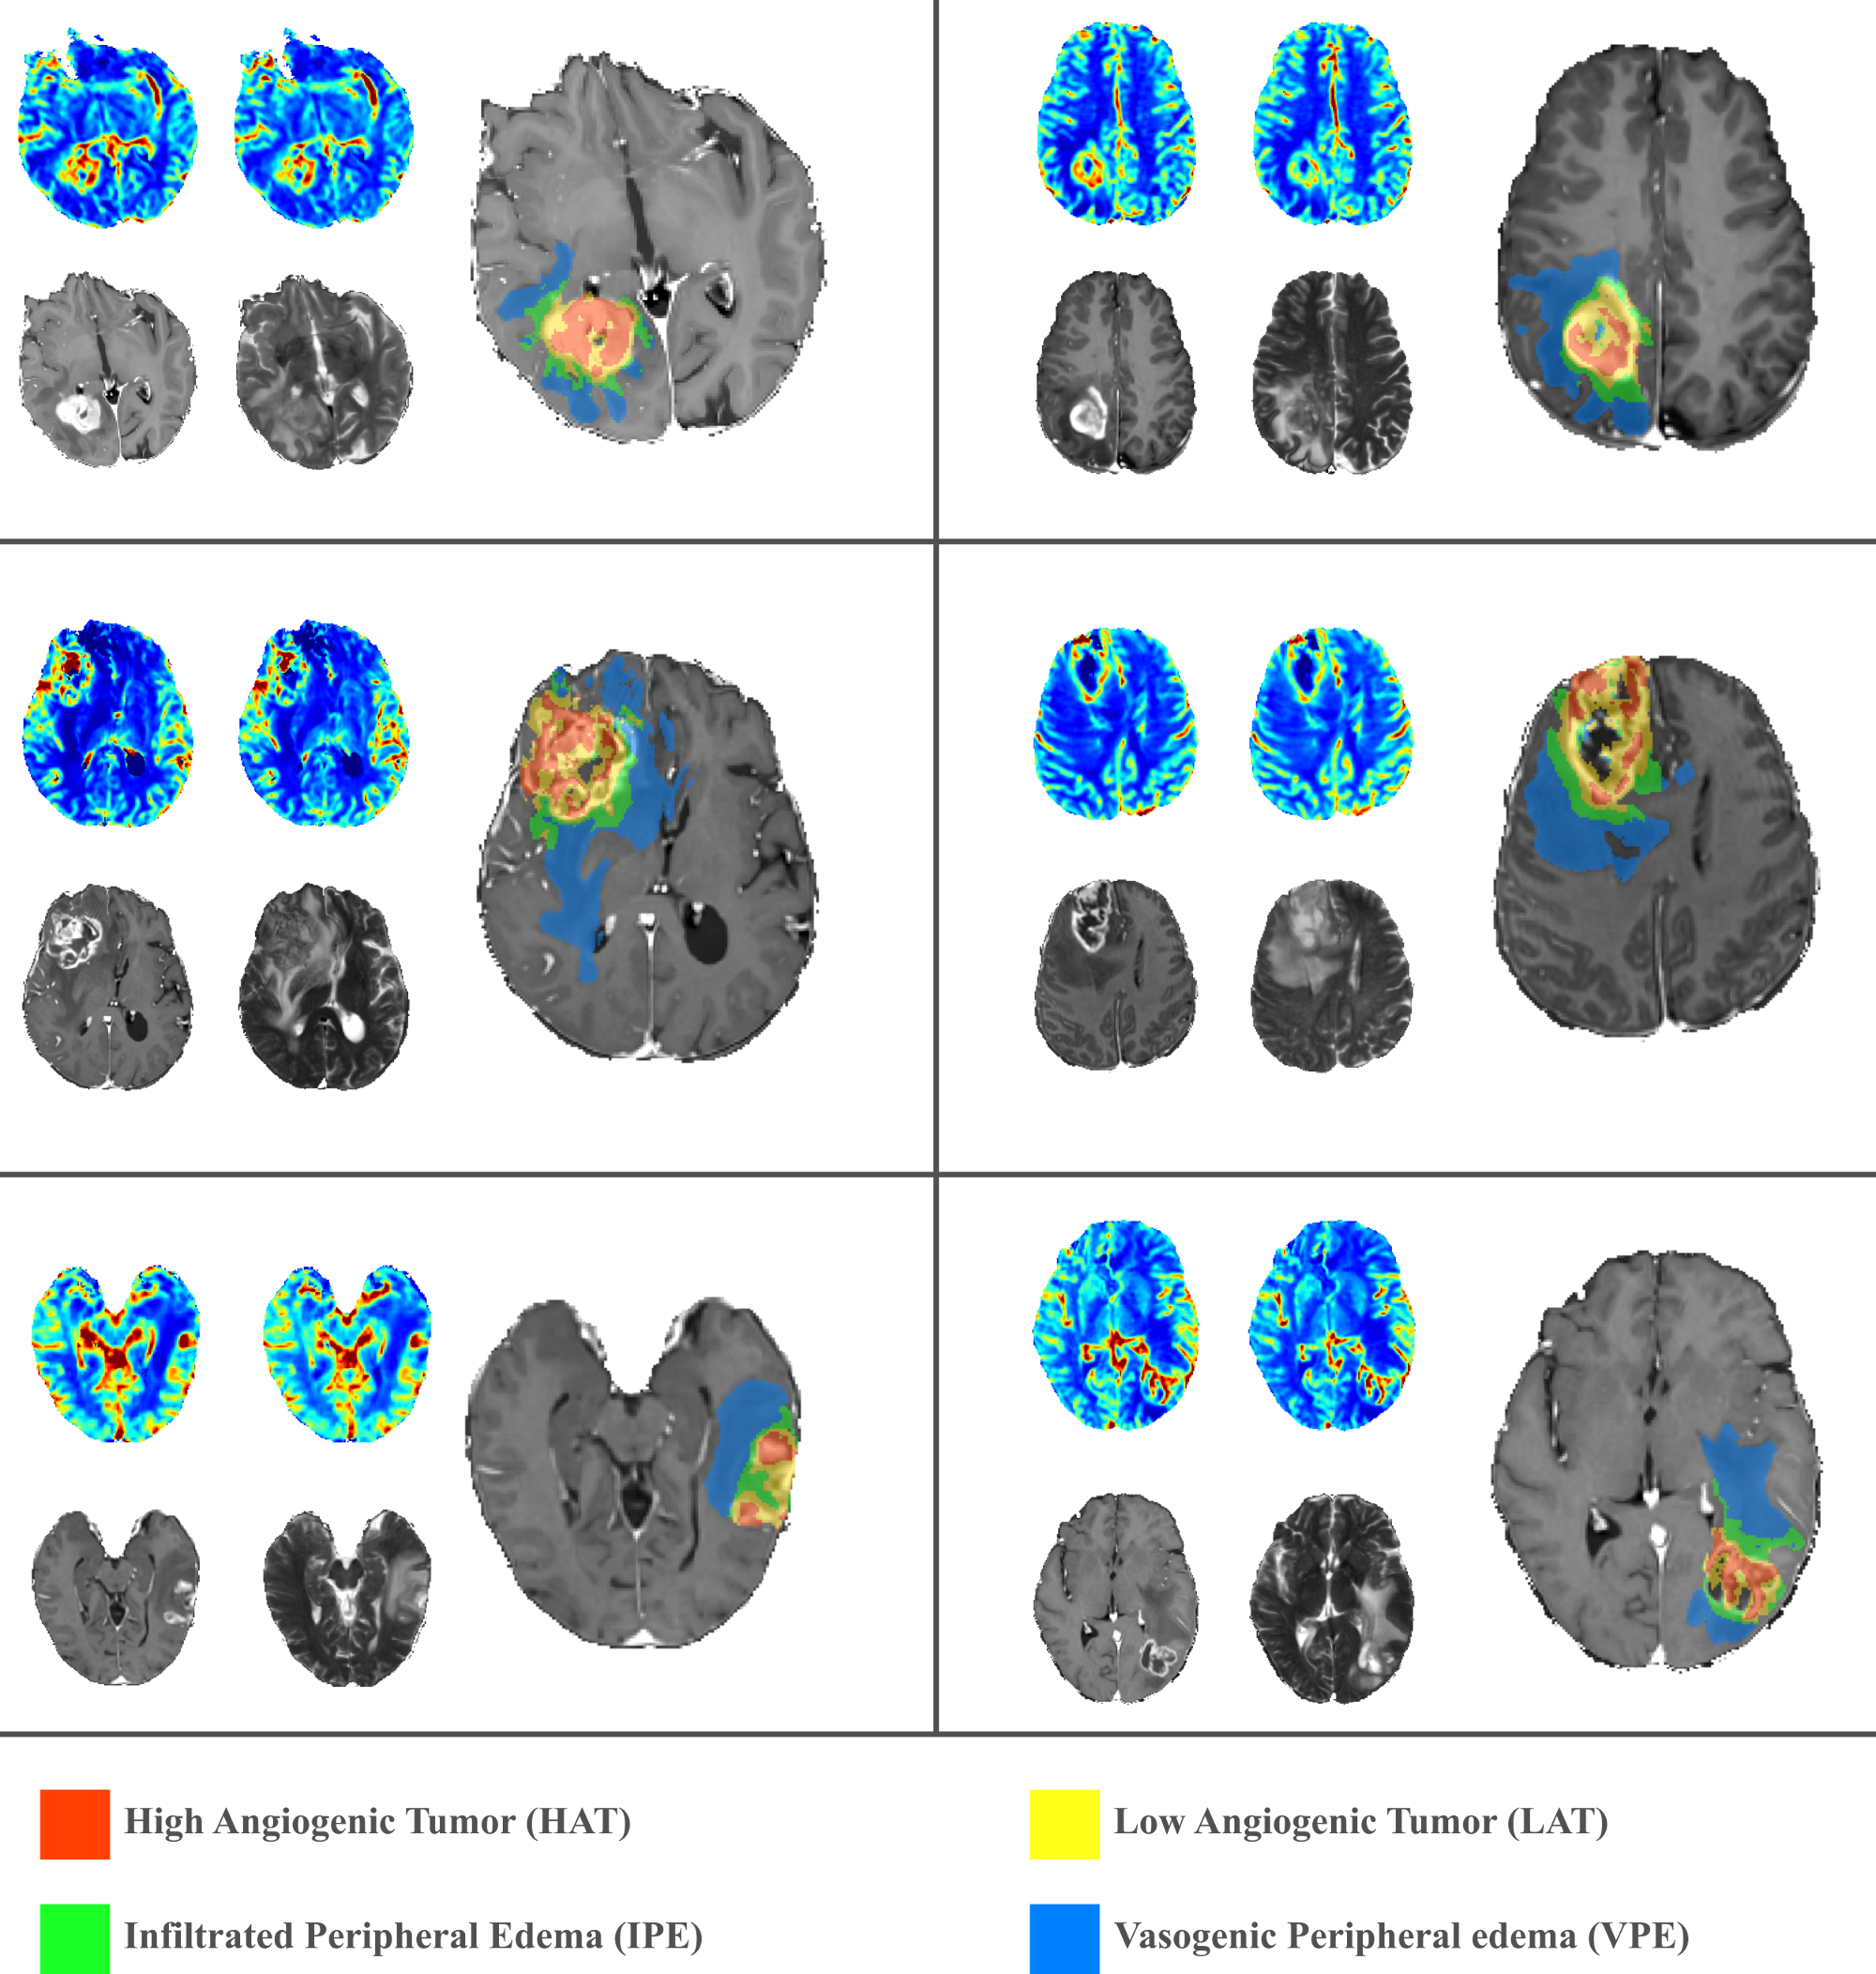

This thesis focuses on the research and development of the Hemodynamic Tissue Signature (HTS) method: an unsupervised ML approach to describe the vascular heterogeneity of glioblastomas by means of perfusion MRI analysis. The HTS builds on the concept of habitats. A habitat is defined as a sub-region of the lesion with a particular MRI profile describing a specific physiological behavior. The HTS method delineates four habitats within the glioblastoma: the High Angiogenic Tumor (HAT) habitat, as the most perfused region of the enhancing tumor; the Low Angiogenic Tumor (LAT) habitat, as the region of the enhancing tumor with a lower angiogenic profile; the potentially Infiltrated Peripheral Edema (IPE) habitat, as the non-enhancing region adjacent to the tumor with elevated perfusion indexes; and the Vasogenic Peripheral Edema (VPE) habitat, as the remaining edema of the lesion with the lowest perfusion profile. The research and development of the HTS method has generated a number of contributions to this thesis.

The Hemodynamic Tissue Signature (HTS) method analyzes the perfusion MRI of a glioblastoma using an unsupervised learning approach to delineate four habitats within the lesion that exhibit different hemodynamic activity. The habitats describe the High Angiogenic Tumor (HAT) and Low Angiogenic Tumor (LAT) regions of the glioblastoma, and the potentially Infiltrated Peripheral Edema (IPE) and Vasogenic Peripheral Edema (VPE) of the lesion. Such approximation establishes a conceptual frame for the description of the tumor heterogeneity by means of the detection of clinically relevant sub-regions, a.k.a habitats, with differentiated imaging biomarkers. The preliminar results of this work were first presented in the conference contribution P4 (Juan-Albarracín et al, 2016) and it was finally published in the journal contribution P5 (Juan-Albarracín et al, 2018).